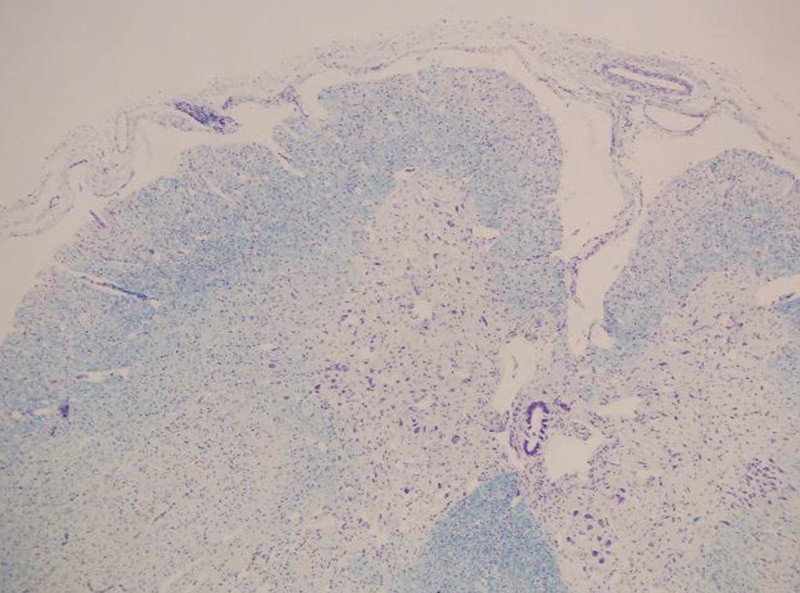

Ved obduksjon ble det funnet tynn diafragma, på kun 1 – 2 mm. Det var svinn av forhornceller i medulla spinalis (fig 1), med usedvanlig små fremre røtter (fig 2). Det var også mulig fibersvinn i kortikospinale baner gjennom hele hjernestammen og i tractus corticospinalis lateralt i medulla. I diafragma fantes spredte grupper av atrofiske fibre og spredte hypertrofiske fibre (fig 3). I skjelettmuskulatur fantes områder med muskelatrofi (fig 4). Det ble fortsatt konkludert med en variant av Werdnig-Hoffmanns sykdom.

De nevropatologiske funn hos disse pasientene varierer. Hos alle finner man muskelatrofi, og mange beskriver forandringer i perifere nerver. Selv om tilstanden oppfattes som spinal muskelatrofi, har ikke alle funnet de forandringer i medullas forhornceller som man ville vente (7). Hos våre pasienter som ble undersøkt, beskrives svinn av nevroner. Både nevropatologiske funn og nevrofysiologiske resultater tyder på perifer aksonal affeksjon og/eller progredierende affeksjon av både motoriske og sensoriske nevroner, der motoriske nevroner blir tidligst og mest affisert.